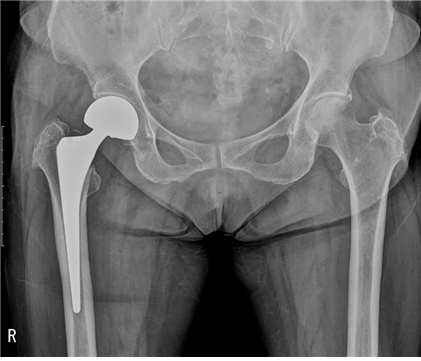

퇴행성 고관절염 초기에는 소염 진통제, 연골 보호제 등 약물 치료와 휴식, 적당한 운동을 병행하며 경과를 살피고 치료를 해야 해요. 고관절 통증 증상이 완화되지 않다면 관절 수술을 해야 해요.

고관절 통증 증상의 진단과 치료 플랜은 통증부위를 중심으로 한 검사부터 시작돼요. 골반과 엉덩이 허리 등의 X-ray 촬영을 진행 골반이 틀어져 있지는 않은지 내부 구조적으로 불균형이나 문제 사항은 없는 지 등을 확인해요.

이어서 환자가 느끼는 통증의 정도를 평가한 뒤 이학적 검사로 고관절의 회전 정도 등을 파악해요. 더불어 필요한 경우에는 초음파검사, CT나 MRI 검사를 진행할 수도 있어요. 이후 수술이 필요한 심각한 상황이 아니라면 비수술적 요법인 프롤로 주사 등이 주로 진행돼요.